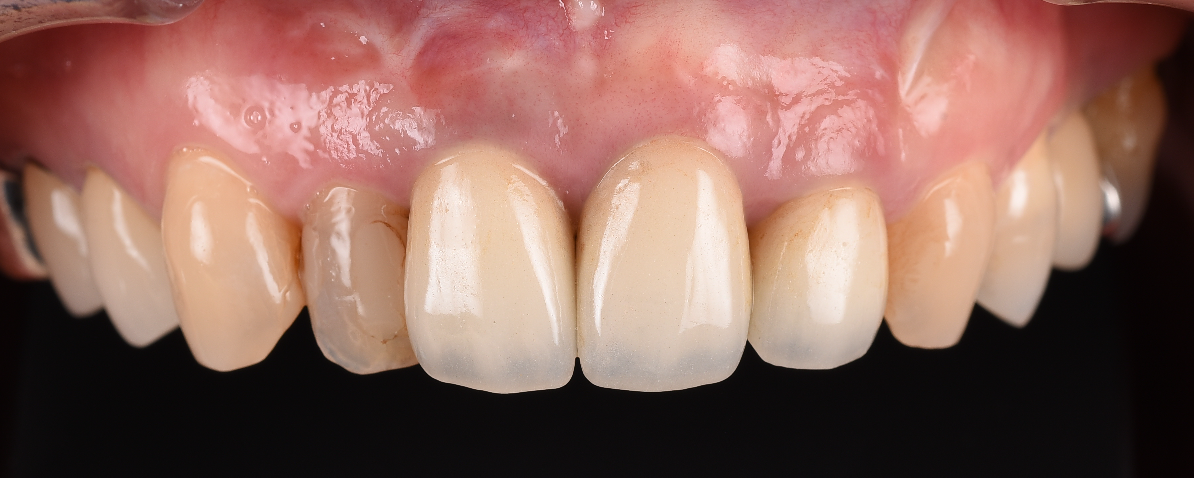

今日は前歯のインプラントの7年経過をみて頂きます。

結合組織の移植も行い、審美性を狙って行いました。

現在7年経過しても問題ありません。

7YEAR